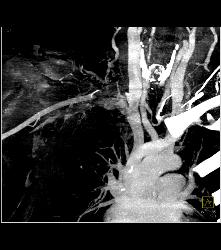

Cervical Rib With Occlusion of the Right Subclavian Artery- See Full Sequence